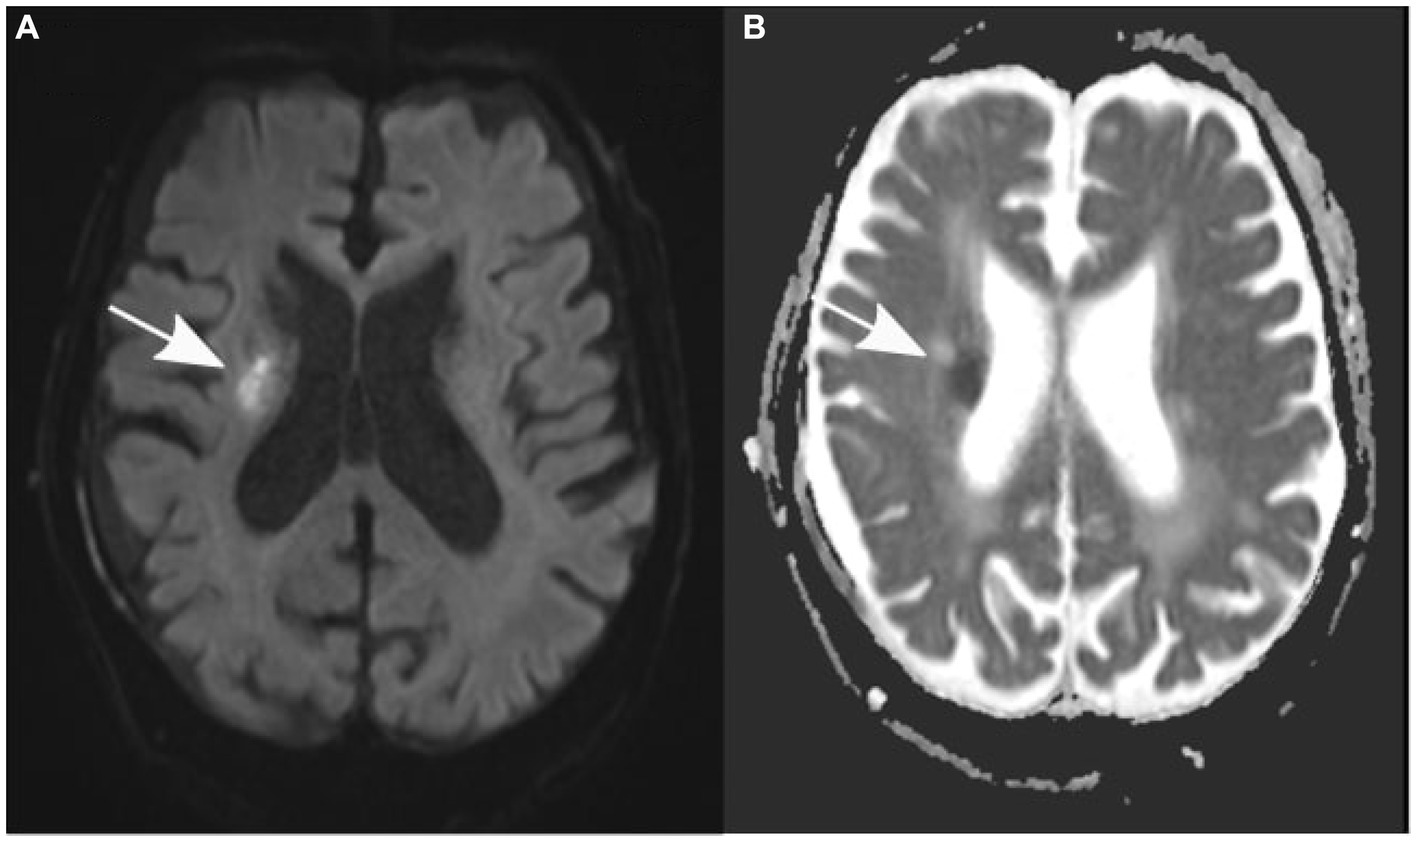

After the patient underwent successful surgery, he was transferred to the standard ward for postoperative monitoring. Nevertheless, the following morning, the patient displayed new neurological symptoms, such as dysarthria and exacerbated left-sided hemiparesis. A subsequent cranial CT scan verified the correct positioning of the subdural drain and revealed a decrease in the size of the subdural hematoma (Figure 1B). Sudden onset of dysarthria and worsening hemiparesis on the left side during the postoperative phase necessitated further imaging. Follow-up cranial CT revealed a decrease in the size of the subdural hematoma; however, this could not explain the aggravated neurological symptoms. An MRI scan of the brain revealed the coexistence of an ischemic stroke in the hyperacute phase of the right corona radiata in the supply area of the right anterior choroidal artery. It exhibited increased brightness on diffusion-weighted imaging (DWI) and reduced apparent diffusion coefficient (ADC) values (Figure 2). Further neurological assessment revealed moderate stenosis of the left middle cerebral artery in the distal M1 segment. A pivotal clinical challenge that has emerged is the lack of clear guidelines on the timing of antithrombotic restart following the occurrence of SDH. This challenge was further compounded by the high risk of very early stroke (within 24 h) in our patient, who presented with recurrent TIAs suggestive of CWS. Given this high risk, the immediate initiation of secondary prevention is a critical consideration. However, considering the recent surgery and the absence of large intracranial artery occlusion, no antithrombotic treatment was initiated.

Figure 2

Axial diffusion-weighted magnetic resonance images (A) show an elevation in signal, while apparent diffusion coefficient values (B) are decreased in the right corona radiata (indicated by an arrow).